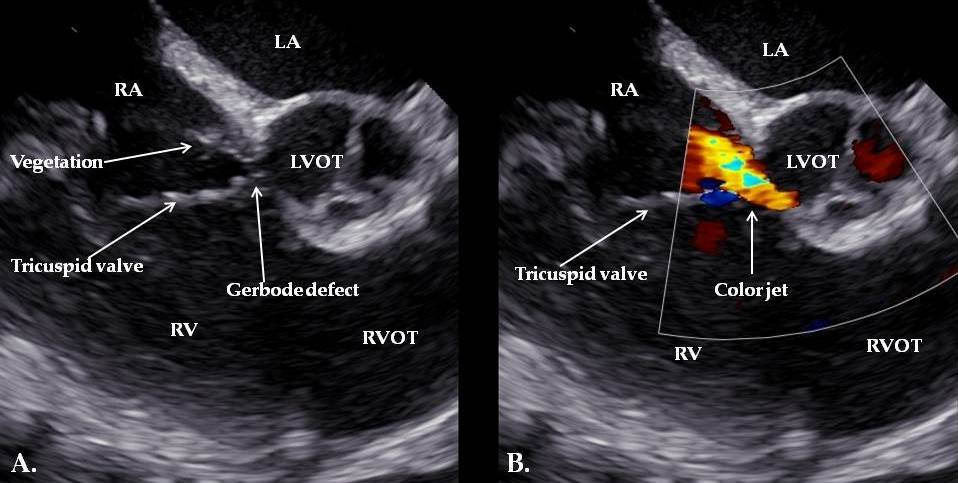

| Day 3 | Diagnosis of IE | Persistent fever, systemic inflammation | TEE: Gerbode defect with a vegetation attached near the tricuspid valve and others involving the tricuspid valve and the pacemaker lead | |